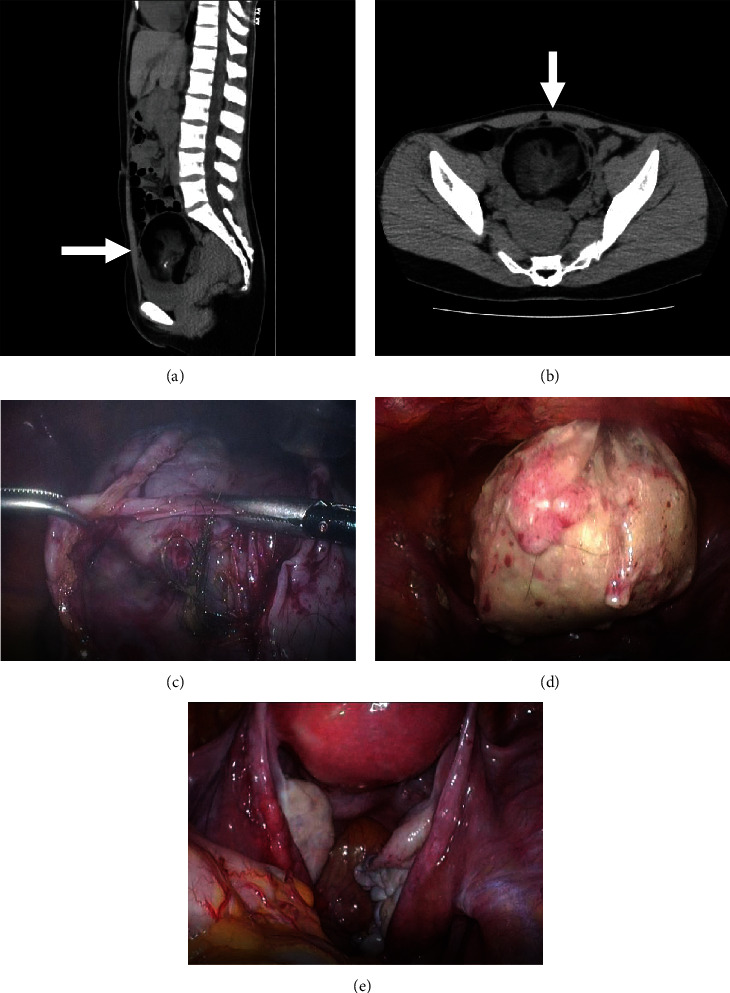

Although laparoscopic cystectomy is a safe and effective management strategy for ovarian mature cystic teratoma (MCT) in pediatric and adolescent patients, it has been challenged because of its association with a higher risk of intraoperative spillage leading to chemical peritonitis, adhesion formation, and iatrogenic implantation of malignant cells. Here, we report a rare case of a 23-year-old female patient with MCT tissue during laparoscopic ovarian cystectomy that remained in the peritoneum, possibly becoming malignant thereafter. Intraoperatively, the cyst's contents leaked into the abdominal cavity. The abdominal cavity was thoroughly cleaned before the operation was completed. Pathological examination revealed an MCT without malignant findings. The patient's postoperative course was uneventful. Although the excised tissue was benign, the patient presented with a mass at the trocar wound (upper suprapubic area) 2 years after initial surgery. Biopsy results indicated squamous cell carcinoma. Moreover, peritoneal and bladder invasions were diagnosed. She subsequently experienced symptoms of cancerous peritonitis. Achieving a complete cure through surgery alone was deemed difficult; however, successful neoadjuvant chemotherapy and tumor reduction surgery kept her alive up until the publication of this case report, 3 years since diagnosis with squamous cell carcinoma. This case indicates that malignant transformation of MCTs can occur at any age.